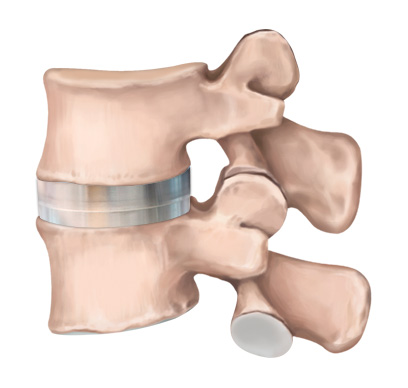

인공디스크 치환술은 손상된 디스크를 제거한 후 척추체 사이에 인공디스크를 삽입하여

본래의 디스크처럼 정상적인 기능을 하도록 하는 수술입니다.

손상된 경추 디스크를 모두 제거하고 빈 공간으로 인공디스크를 삽입하여 본래의 디스크처럼 정상적인 기능을 하도록 합니다.

인공디스크 삽입

척추 움직임이 정상 디스크와 유사하여 움직임이 매우 자유롭습니다.